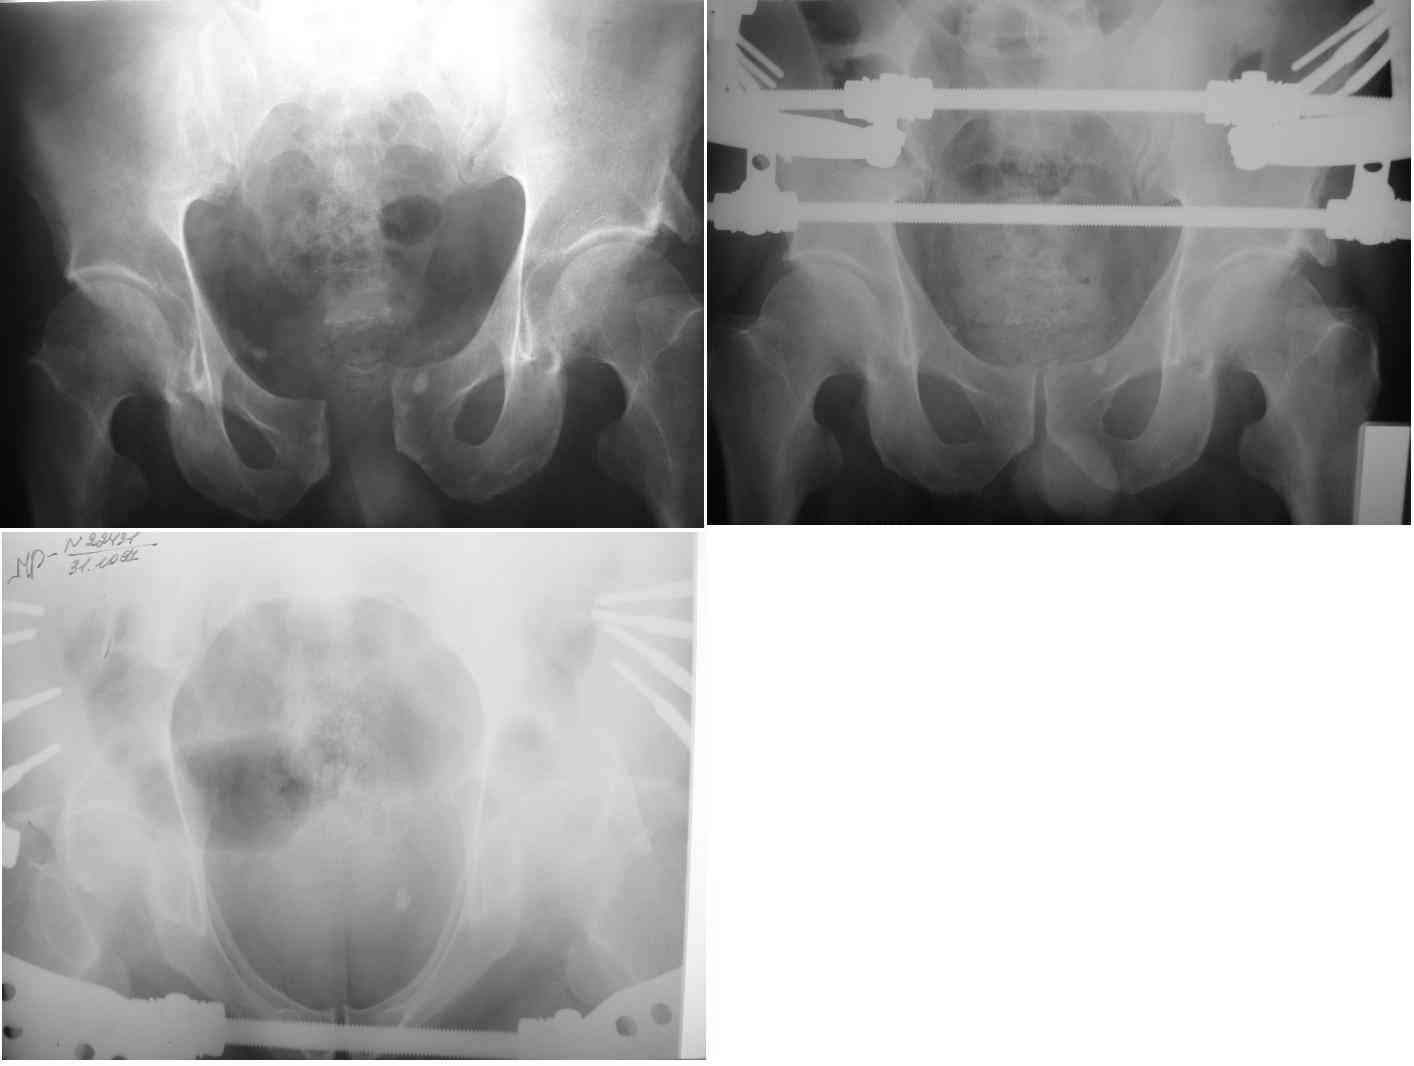

Re: разрыв лонного сочленения

извините за опоздание , вот фотографии